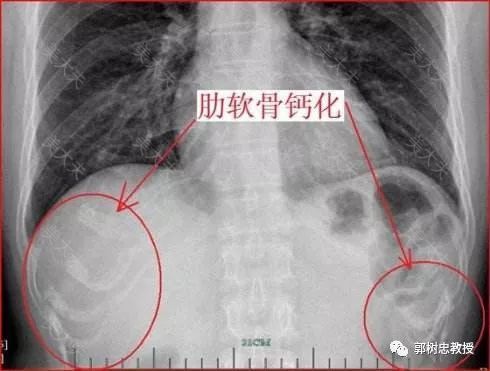

我自己的病例返修的很少,但我接诊过不少其他医生手术后因为外形过于难看而找我翻修的病人,这些患者有的是术后数月,有的是术后数年,取出的肋软骨支架多数可以再利用,这些软骨做新支架的底座没有什么问题,所谓的肋软骨钙化也并非常见,即使遇到钙化也无法判断是做耳朵之前肋软骨就钙化了,还是造完耳朵后发生的钙化。

在临床上我们倒是遇到过极少数肋软骨本身已经钙化的病例,这个时候支架雕刻会困难一些,但远期效果并没有出现什么问题,多数还是能够维持早期的形状。